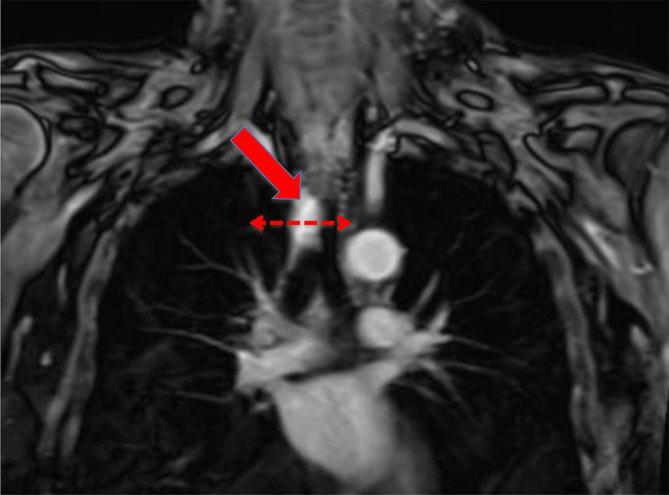

MRI of a recurrent adenoid cystic carcinoma of the trachea, treated with fast neutron therapy.

Adenoid cystic carcinoma (ACC) of the trachea is a rare tumour, which responds well to high linear energy transfer radiation, such as neutron therapy. Both CT and MRI are useful for its diagnosis, with MRI being superior at determining the extent of disease and perineural involvement. Identification of these disease characteristics with MRI helps to determine lesion resectability and decide on the most appropriate treatment strategies. MRI is also useful in the differentiation of post-radiation change from disease recurrence, with post-radiation change displaying low signal intensity compared with tumour recurrence displaying intermediate to high signal intensity. Furthermore, MR diffusion-weighted imaging can be useful in the distinction between the two. We present a case of tracheal ACC treated with fast neutron therapy and followed with MRI.